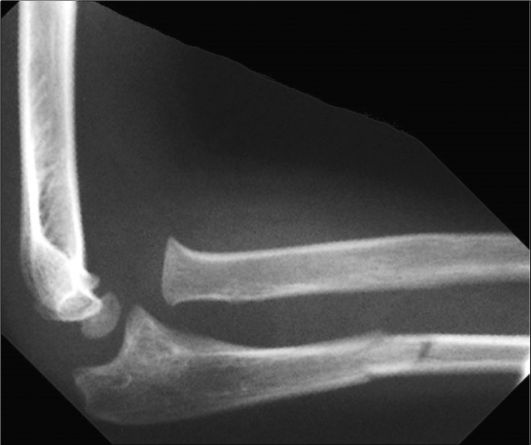

Переломы и вывихи являются одной из самых частых причин направления пациентов на лучевое исследование (чаще всего - рент- генографию). Перелом - это нарушение анатомической целостности кости (рис. 3-10). Вывих - смещение суставных поверхностей костей по отношению друг к другу (рис. 3-11).

Рис. 3-11. Вывих локтевого сустава